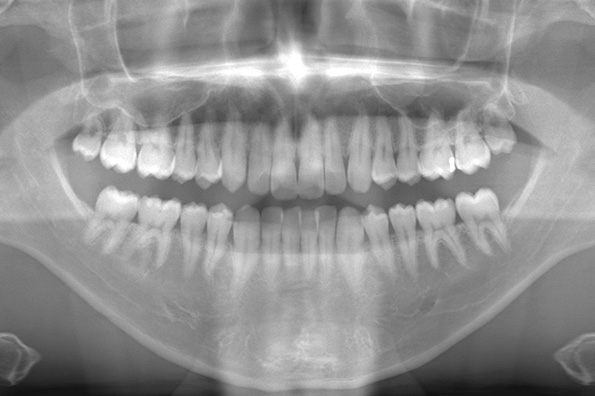

CASE 1

基本情報

| 年齢・性別 | 30代・女性 |

| 主訴 | 左右に分けて親知らずを抜きたい、できれば痛くなく抜きたい |

| 親知らずのはえ方 | 完全に出ていてまっすぐはえている |

| 抜歯期間 | 15分 |

| 抜歯費用 | 約2,000円(保険内) |

| 抜歯内容 |

何度か虫歯になり痛みはないが早めに抜きたい。 完全に頭が出ているため歯ぐきを切ったり骨を削らずに抜歯しました。 根の形も単純なため抜歯自体は5分もかからず上下ともに終わりました。 術後痛みや腫れも出ていません。 抜歯後は感染をしやすいため必ず抗生物質を飲み切ってください。 |